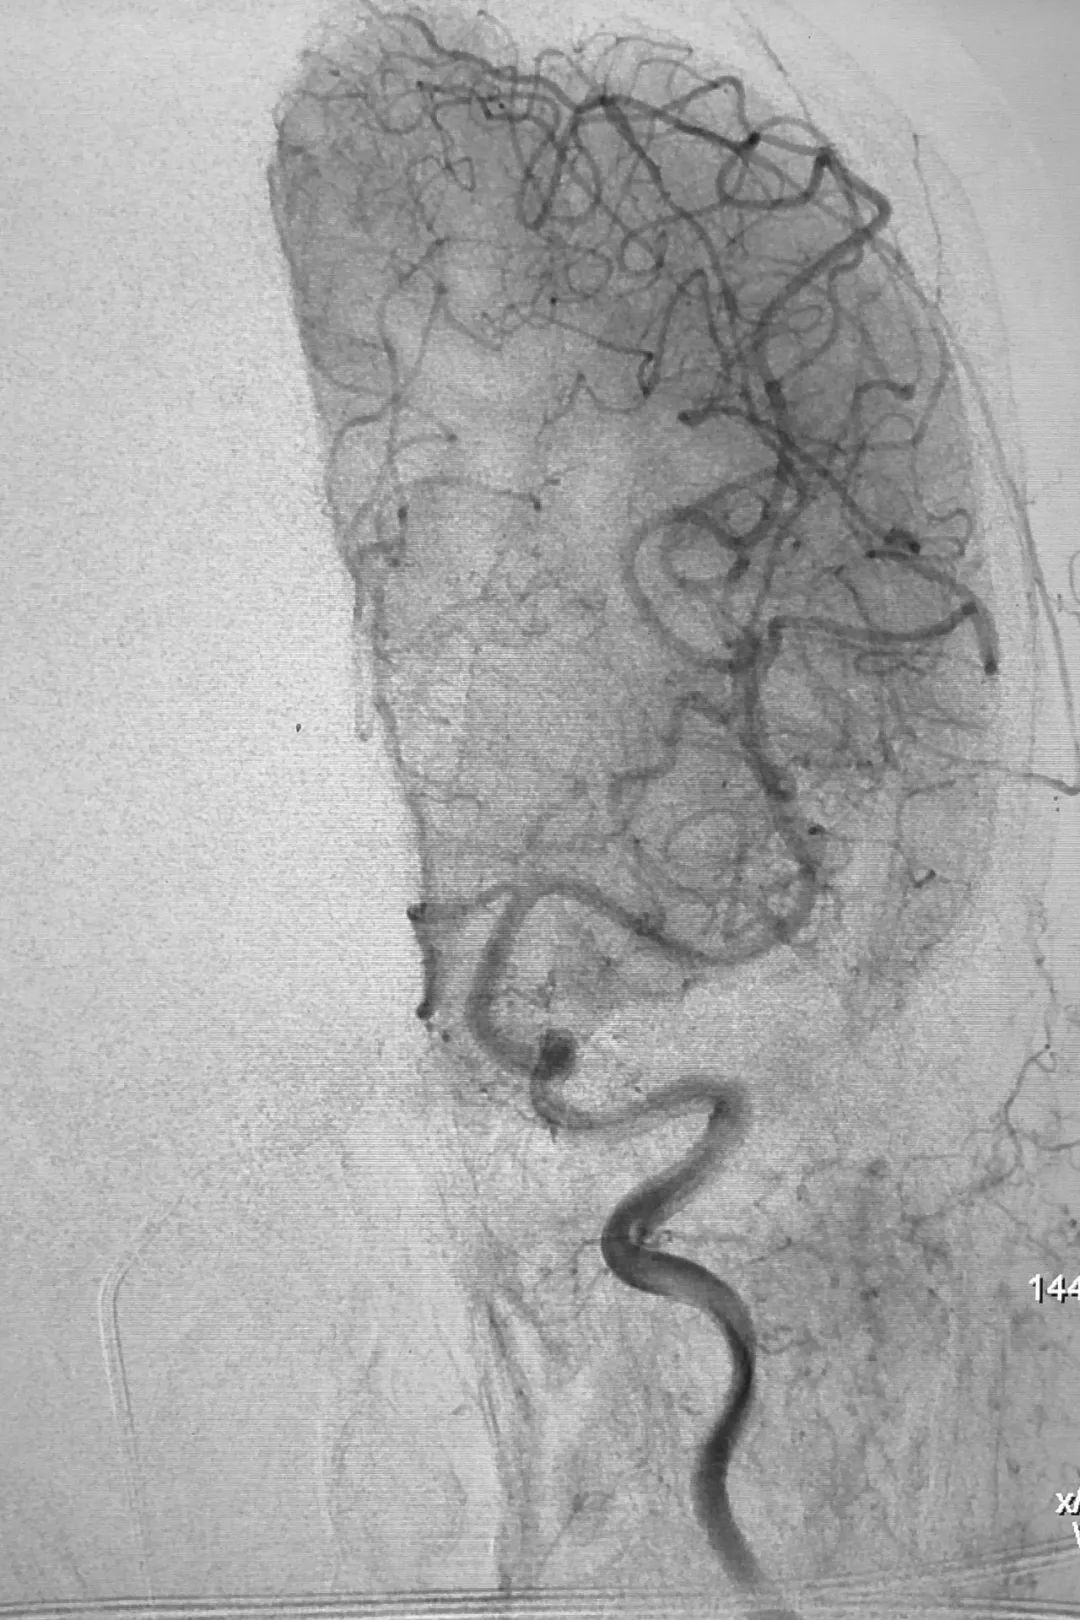

② 撤出6F Envoy导引导管,换用5F单弯造影管(强生),在泥鳅导丝引导下轻松对接右侧岩下窦,此处利用了强生单弯造影管强硬的支撑力和单弯的指向。在左侧颈总动脉正位路图指示下,Echelon-10微导管+Synchro-14微导丝经造影管送入右侧岩下窦,并长驱直入右侧海绵窦:

③ 微量造影正、侧位显示Echelon-10微导管管头位置适宜,位于右侧海绵窦前部、眼上静脉根部: